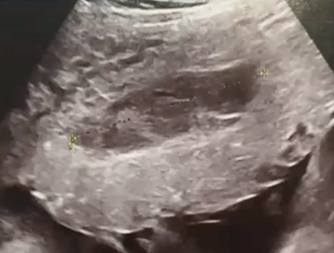

Mme G. est finalement césarisée sous anesthésie générale sans complication. Lors de l’hystérotomie, le liquide amniotique est sanglant avec de nombreux caillots. Les pertes sanguines sont estimées à 1 500 mL. L’équipe d’anesthésie a administré en peropératoire un culot de globules rouges et un plasma frais congelé (PFC), ainsi que de l’acide tranexamique. L’utérus est tonique en fin d’intervention. Au cours de la surveillance en salle de surveillance post-interventionnelle (SSPI), à quatre heures postopératoires, Mme G. a une barre épigastrique résistante aux antalgiques de palier 3. Les constantes sont les suivantes : pression artérielle = 190/110 mmHg ; fréquence cardiaque = 120 bpm ; saturation en oxygène = 99 % en air ambiant. Compte tenu de la tachycardie, vous réalisez une échographie transabdominale dont les images sont les suivantes. Figure 2a (Rodolphe Matias de Sousa, La Revue du Praticien)Figure 2b (Rodolphe Matias de Sousa, La Revue du Praticien)Figure 2c (Rodolphe Matias de Sousa, La Revue du Praticien) Vous décidez d’avancer le prochain bilan biologique et récupérez les résultats suivants : hémoglobine = 8,7 g/dL ; plaquettes = 40 G/L ; TP = 65 % ; TCA = 1,02 ; fibrinogène = 2 g/L ; haptoglobine indosable ; ASAT = 260 UI/L ; ALAT = 240 UI/L.

Concernant l’hématome sous-capsulaire du foie : Tableau 3 (Rodolphe Matias de Sousa, La Revue du Praticien) Concernant l’échographie transabdominale à la recherche d’un hémopéritoine :on regarde deux espaces, le cul-de-sac de Douglas entre l’utérus et le rectum, et l’espace de Morrison entre le foie et le rein. Figure 3a (Rodolphe Matias de Sousa, La Revue du Praticien)Figure 3b (Rodolphe Matias de Sousa, La Revue du Praticien)Figure 3c (Rodolphe Matias de Sousa, La Revue du Praticien) Pour rappel, concernant l’échographie en gynécologie : Figure 4a (Rodolphe Matias de Sousa, La Revue du Praticien)Figure 4b (Rodolphe Matias de Sousa, La Revue du Praticien)Figure 4c (Rodolphe Matias de Sousa, La Revue du Praticien)Figure 4d (Rodolphe Matias de Sousa, La Revue du Praticien)Figure 4e (Rodolphe Matias de Sousa, La Revue du Praticien)Figure 4f (Rodolphe Matias de Sousa, La Revue du Praticien)Figure 4g (Rodolphe Matias de Sousa, La Revue du Praticien)Figure 4h (Rodolphe Matias de Sousa, La Revue du Praticien)Figure 4i (Rodolphe Matias de Sousa, La Revue du Praticien)